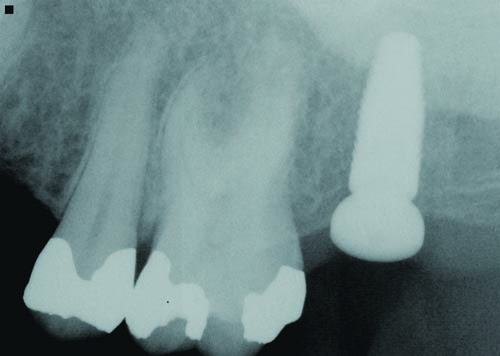

Figs. 30–32: Two weeks later, the fourth appointment was reserved for restoration try-in and final impressions on the endosteal implants. It was during the fifth appointment, scheduled for two weeks later, that the implant-supported IPS E.max crown restorations were delivered, as well as the other definitive maxillary restorations, and any necessary adjustments made. These postoperative radiographs confirmed healing at the #3, #12 and #15 sites, which were all ultimately restored with Straumann implants, custom titanium abutments and IPS E.max crowns.